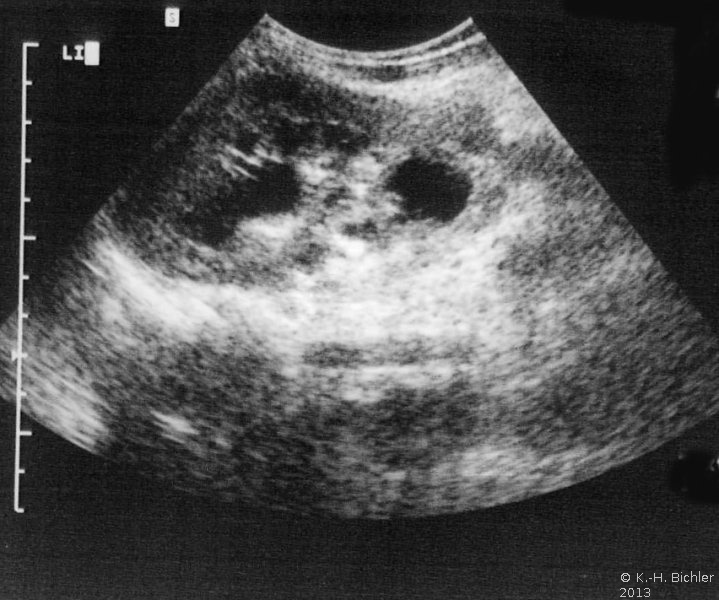

Sonographiebeispiele: Harnstau infolge Ureterabgangsstenosen (Abbildung 6a,b).